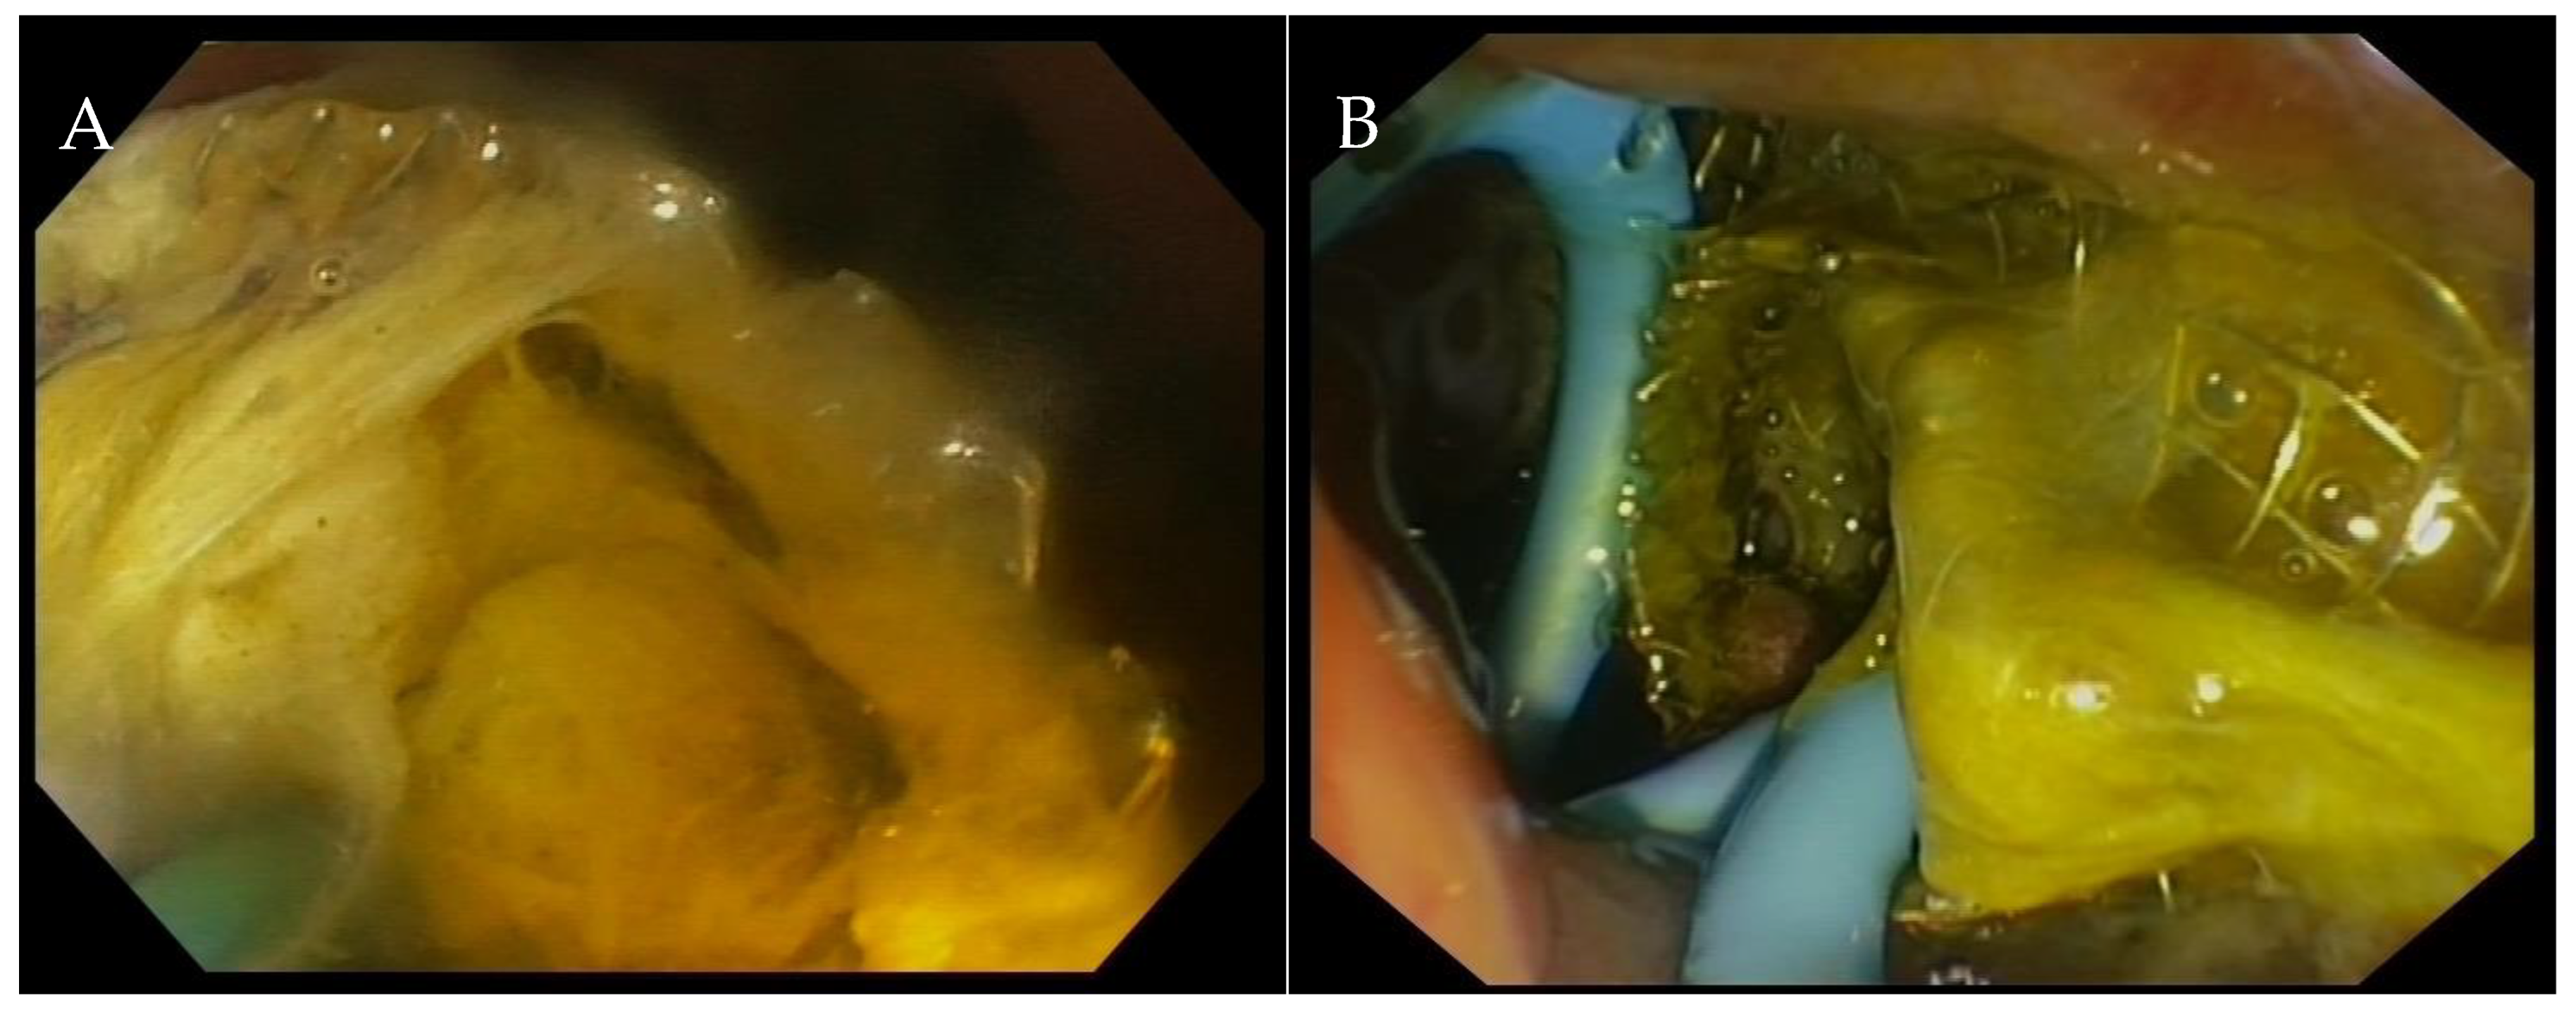

3. EUS-Guided Gallbladder Drainage: Technical Aspects

- Chan, S.M.; Teoh, A.Y.B.; Yip, H.C.; Wong, V.W.Y.; Chiu, P.W.Y.; Ng, E.K.W. Feasibility of per-oral cholecystoscopy and advanced gallbladder interventions after EUS-guided gallbladder stenting (with video). Gastrointest. Endosc. 2017, 85, 1225–1232. [Google Scholar] [CrossRef] [PubMed]